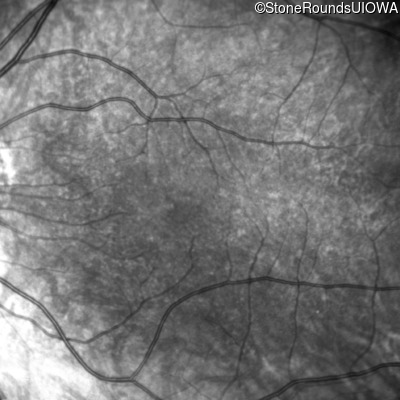

Infrared Fundus Photograph - Right - 10/160 sc

Exemplar

Infrared Fundus Photograph - Left - 10/200 sc